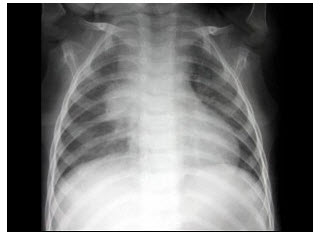

20、单项选择题

男,12岁,平时无明显不适,结合图像,最可能的诊断是()

A.正常胸片

B.左旋心

C.右旋心

D.镜面右位心

E.以上都不是